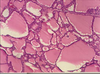

What are foam cells?

Macrophages whos cytoplasm appears foamy from phagocyting a lot of lipid.